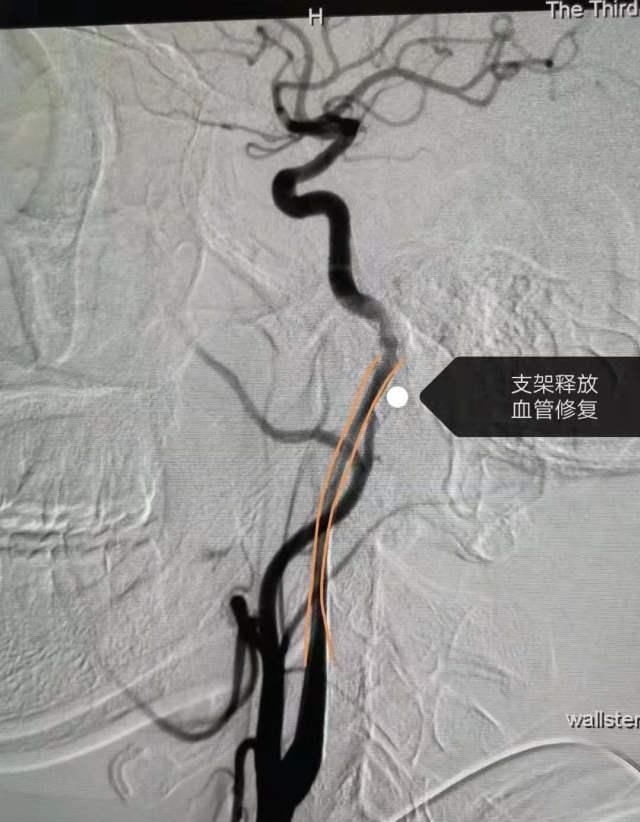

"这是因为颈部按摩或刮擦会诱发颈动脉夹层马跃说,经过对比检查,医生确认赵雷的右颈内动脉有一个大约7厘米的夹层。手术后,病灶血管已经修复目前,赵雷正准备出院,身体状况良好。回顾整个过程,赵雷和他的家人仍然心有余悸

医院神经外科主任黄立金说,动脉夹层会使血液渗透到血管层之间,造成动脉狭窄甚至完全阻塞管腔,导致缺血性神经系统症状的出现目前,颈动脉夹层是中青年患者中风的重要原因。